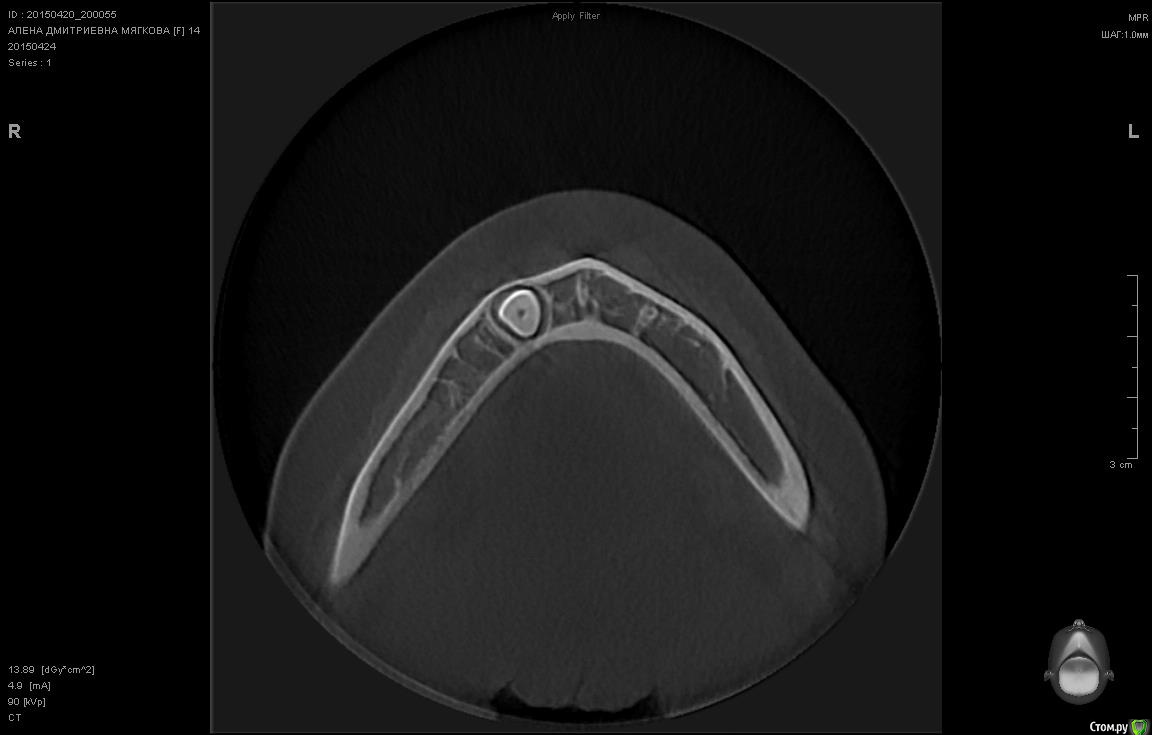

sgeorge Опубликовано 24 апреля, 2015 Автор Поделиться Опубликовано 24 апреля, 2015 КТ сделали, срезы выложу Ссылка на комментарий

voff Опубликовано 24 апреля, 2015 Поделиться Опубликовано 24 апреля, 2015 по кт смотреть где ближе к кортикалке, там и подбираться Ссылка на комментарий

sgeorge Опубликовано 24 апреля, 2015 Автор Поделиться Опубликовано 24 апреля, 2015 Вот некоторые срезы. Вопрос в том, стоит ли браться за ортодонтию. Ортодонта сегодня нет, спросить не могу. Ссылка на комментарий

sgeorge Опубликовано 24 апреля, 2015 Автор Поделиться Опубликовано 24 апреля, 2015 Как-то криво прикрепились, сорри.Думаю, что с таким крючком на апексе ортодонтия отпадет? Тогда стоит ли удалять в настоящий момент или дождаться завершения роста челюсти? Ссылка на комментарий

krokomot Опубликовано 24 апреля, 2015 Поделиться Опубликовано 24 апреля, 2015 Клык то молочный во рту, без ортодонтии все равно не обойтись так что можно попробовать зуб вертикально почти стоит, только кортикалку желательно бы удалить по ходу выдвижения (постепенно). На стрелке думаю одонтома при раскрытии убрать. Ссылка на комментарий